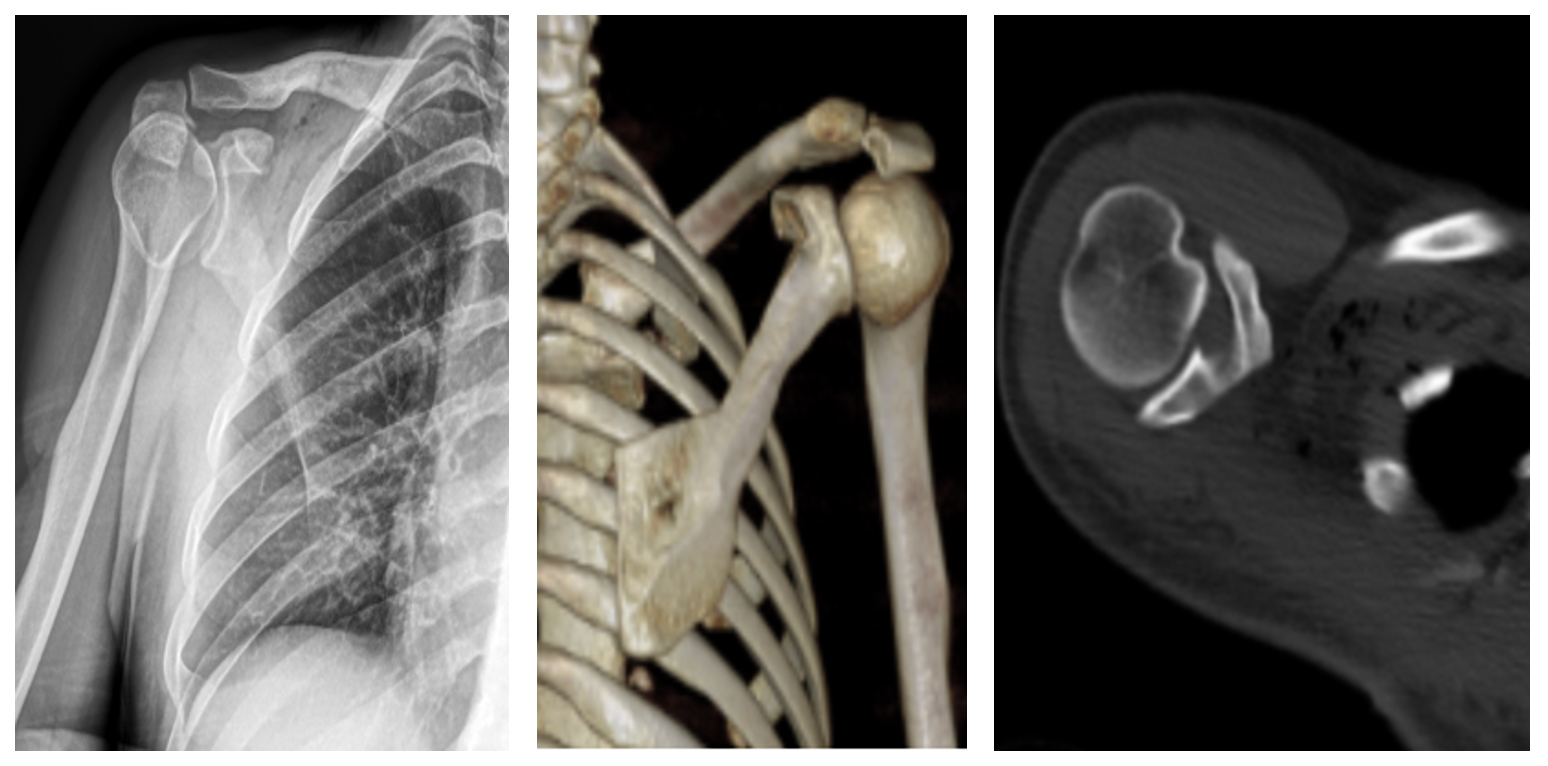

Ameliyat Öncesi: Röntgende skapula üzerinde düzensiz sınırlı heterojen kitle görünmekte.

Ameliyat Öncesi: Tomografide skapulada harabiyet ve kıkırdak doku görünmekte.

Ameliyat Sonrası: Röntgende ve tomografide tümör çıkarıldıktan sonra kalan skapula görülmekte.